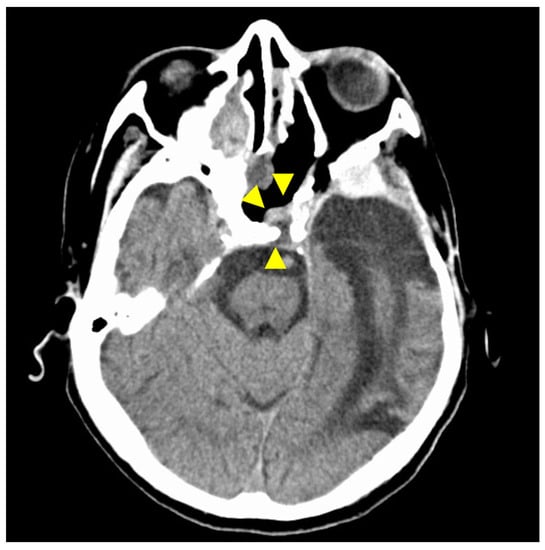

Figure 4. Postoperative T1-weighted contrast-enhanced MRI findings. Axial section (A) and coronal (B) images are shown. The tumor is confirmed to be resected along with the ICA. Arrowheads indicate the site of tumor removal.

A multidisciplinary team of otolaryngologists and neurosurgeons performed a complete resection of the tumor using a simultaneous combined transcranial and transnasal approach that utilized high-flow radial artery bypass between the M2 segment of the left middle cerebral artery (MCA) and the left cervical external carotid artery with an additional superficial temporal artery–MCA bypass. The margin of tumor resection was determined by a rapid intraoperative diagnosis to confirm the tumor extent. The ICA was trapped under blood flow preservation bypasses, enabling complete resection of the tumor along with the ICA (Figure 4). The ocular artery and cranial nerves III–VI were preserved. The skull base was reconstructed using two layers of the temporalis muscle and a vascular pedicle nasoseptal flap. Magnetic resonance angiography was performed immediately after the surgery, indicating adequate blood flow through the bypasses (Figure 5). The postoperative immunohistochemistry results were positive, similar to the biopsy immunoprofile (Figure 6). In addition, there were no S-100 protein-positive sustentacular cells around the tumor cells. Differentiating between high-grade ONB and neuroendocrine tumors is sometimes difficult; the tumor was eventually diagnosed as NEC, based on the absence of sustentacular cells and the absence of morphological findings such as Homer–Wright rosettes (Figure 6D).